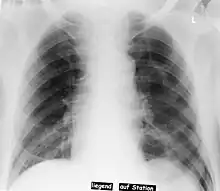

Deep sulcus sign

Pneumothorax left sided

Differential diagnosispneumothorax

In radiology, the deep sulcus sign on a supine chest radiograph is an indirect indicator of a pneumothorax.[1][2] In a supine film, it appears as a deep, lucent, ipsilateral costophrenic angle[3] within the nondependent portions of the pleural space as opposed to the apex (of the lung) when the patient is upright. The costophrenic angle is abnormally deepened when the pleural air collects laterally, producing the deep sulcus sign.[4]